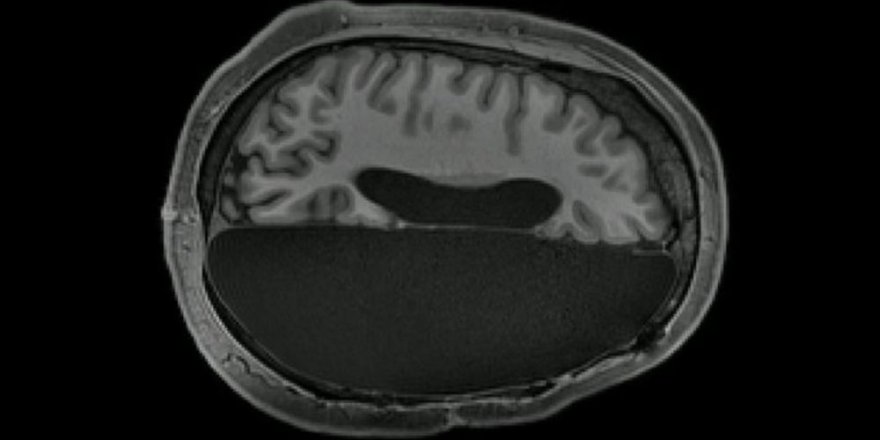

Habere göre bilim insanları, çocukluklarında normal ilaçlarla tedavi edilemeyen şiddetli epilepsi geçiren ve kurtarılmaları için beyinlerinin yarısı alınan 6 hastanın manyetik rezonans tomografisini (MR) çekti.

Ardından araştırmacılar, hasta kişilerin MR sonuçlarını sağlıklı insanlara çekilmiş olan tomografi sonuçları ile karşılaştırdı.

Çalışmanın sonuçları, bir yarım küresi eksik olan insanlarda beynin aktivitesinin, tüm beynin aktivitesi ile büyük bir benzerlik gösterdiğini ortaya koydu.

Bunu kanıtlayan şey ise, tek yarım küredeki nöron ağlarının arasındaki istikrarlı bağlar oldu. Söz konusu bağların tek yarım kürenin eksikliğini kısmen telafi ettiği ve hastanın bilişsel yeteneklerini desteklediği ortaya çıktı.